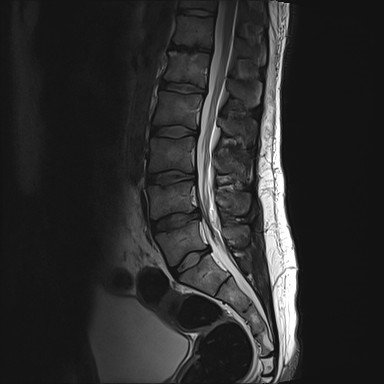

Jako specjalista neurolog zajmuję się diagnostyką i leczeniem przede wszystkim stwardnienia rozsianego oraz innych chorób demielinizacyjnych, a także migreny i innych bólów głowy.

• bóle kręgosłupa,

• rwa kulszowa, udowa, barkowa,